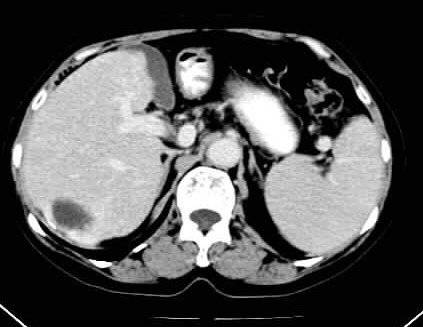

标题: CT24035:肝内占位

1)肝右叶后段血管瘤。2)脾大。

肝右叶后段血管瘤、肝左叶缺如、脾大

肝右叶后段低密度块影,增强后造影剂逐渐向病灶充填,支持肝血管瘤。